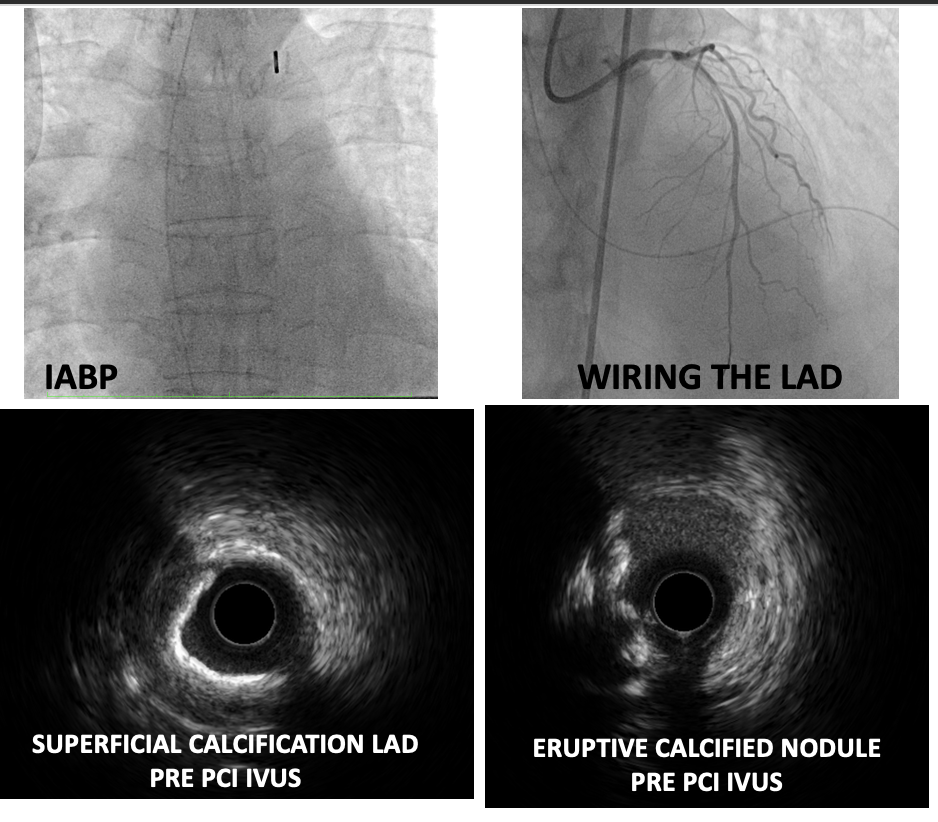

Percutaneous coronary intervention (PCI) of the LMCA-LAD lesion was performed with intra-aortic balloon pump (IABP) support. A 6 French EBU 3.5 guiding catheter was used to engage the left coronary artery. After wiring the lesion with a moderate support wire, intravascular ultrasound (IVUS) revealed an eruptive calcified nodule in the distal LMCA and heavy calcification (270-360 degrees) in the LAD. Rotablation was performed with a 1.5 mm burr for 3 runs. Following rotablation, the LAD wire was lost but successfully rewired. The LMCA-LAD lesion was predilated with a 3.0 x 15 mm non-compliant (NC) balloon. Provisional crossover stenting of the LMCA-LAD was performed with a 3.0 x 38 mm drug-eluting stent (DES). Proximal optimization was achieved with a 4.0 x 8 mm NC balloon inflated to 16 atmospheres (ATM) in the LMCA. The proximal-mid LAD was post-dilated with a 3.0 x 15 mm NC balloon inflated to 12 ATM. Repeat IVUS demonstrated good stent apposition and landing zones with no edge dissection, but the minimal stent area (MSA) in the proximal LAD required further optimization. Final post-dilation in proximal LAD with a 3.5 x 12 mm non-compliant (NC) balloon inflated to 16 ATM resulted in a good final angiographic result and IVUS-confirmed MSA of 8.01 mm2 in the LAD and 12.24 mm2 in the LMCA.

Case Summary

This case highlights successful IVUS-guided PCI with rotablation in a critically ill patient with late-onset STEMI and aVR ST-elevation. The culprit lesion was a complex, eruptive calcified nodule in the distal LMCA, for which now no established treatment strategy exists. Despite the challenges, optimal angiographic and IVUS results were achieved. This case demonstrates the feasibility and potential benefit of this approach in this complex high-risk subset of ACS patients.